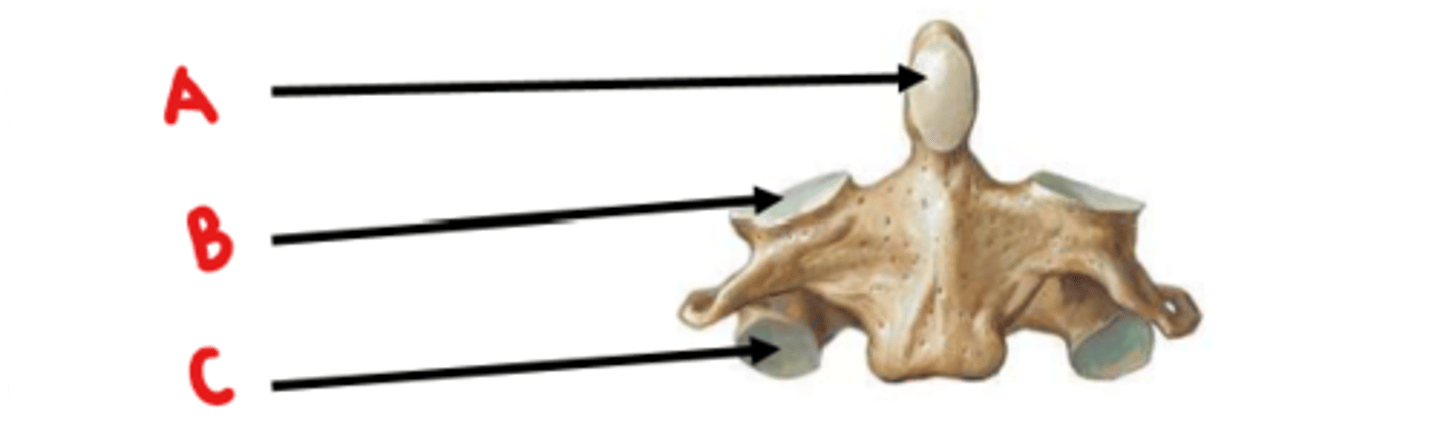

Axis (C2)

What vertebrae is this?

odontoid process (dens)

Identify A

superior articulating facet

Identify B

inferior articulating facet

Identify C